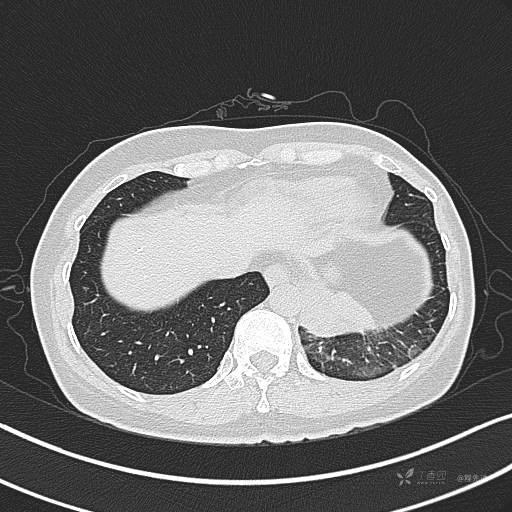

CT平扫

肺窗